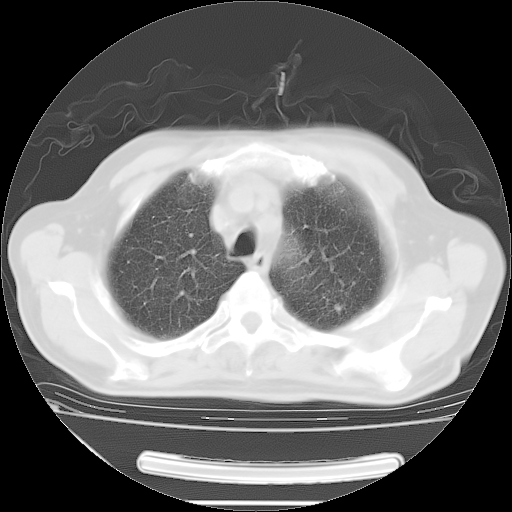

今天复查肺部CT,发现双肺广泛磨玻璃样改变。所以我把3月19日和5月9日相隔50天的肺部CT上传。请大家会诊。

5月9日肺部CT(在4月27日齐鲁医院肺部CT描述部分肺组织磨玻璃样改变,12天后肺组织广泛磨玻璃样改变)

2009年5月9日肺部CT

大致读了系列胸部CT:纵隔窗无明显异常,肺窗:从4、27至今:主要是双肺中下野外带可见毛玻璃样改变,目前处于急性肺泡炎阶段,至于原因考虑1、结替组织或胶原血管性疾病所致?2、恶性疾病如恶组在肺部所致的表现或细支气管肺泡癌?3、药物或其它原因如肺蛋白沉着症所致肺泡炎目前不太可能?总之,明天就去请我院的呼吸科、感染科、血液科和临免专家会诊哈。